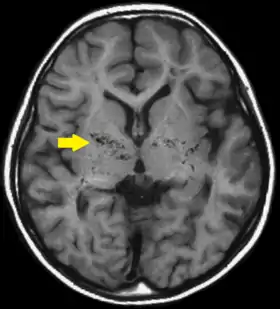

Діагностика ранніх стадій хвороби моямоя утруднена у зв'язку з відсутністю характерних для хвороби симптомів. Однак розвиток транзиторних ішемічних атак або інфарктів мозку у молодому віці дозволяє запідозрити дане захворювання. Загальноклінічні та біохімічні дослідження крові малоінформативні. У план обстеження цієї категорії хворих необхідно включати імуноферментні дослідження. Комп'ютерна томографія і магнітно-резонансна томографія з контрастною ангіографією візуалізують внутрішньочерепні зміни у пацієнтів. При КТ, МРТ головного мозку виявляються неспецифічні вогнища зниженої щільності, які локалізовані в обох каротидних басейнах, атрофічний процес, гідроцефалія або ознаки внутрішньочерепних крововиливів.

Діагноз БММ стає достовірним на основі характерної ангіографічної картини, що складається з двостороннього стенозу або оклюзії інтракраніального відділу внутрішньої сонної артерії і розвиненою колатеральною мережею на основі мозку, що нагадує дим сигарети.